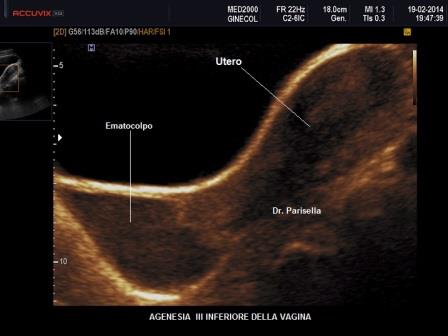

Anche per quanto riguarda le malformazioni vaginali il tipo di anomalia dipende dal periodo in cui avviene il difetto: si va dalle agenesie vaginali alla presenza di setti, alla vagina doppia, all'atresia vaginale.

Anomalie Vaginali

- Aplasie vaginali: sono dovute a difetti di canalizzazione dei dotti di Muller; possono essere totali, in genere con corni uterini rudimentali, o parziali a varia altezza della vagina con i classici sintomi della ritenzione mestruale.